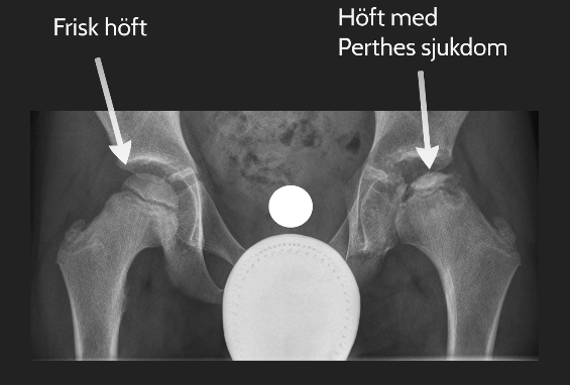

Höft, ljumsk eller knäsmärta vid belastning kan bero på cirkulationsstörning (Perthes sjukdom) eller glidning i tillväxtzonen i höftkulan (Höftfyseolys), det senare kräver akut röntgen och operation inom ett dygn.